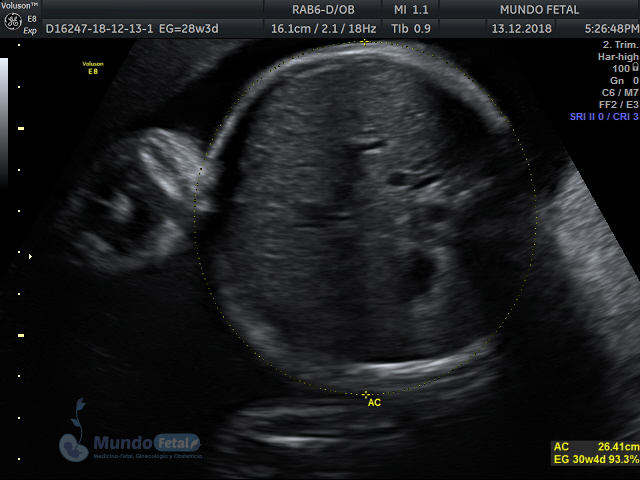

Mediante esta técnica ultrasonográfica, evaluamos en tiempo real al bebe y monitoreamos electrónicamente la frecuencia cardiaca fetal, vigilando los siguientes parámetros:

A cada parámetro se le asigna un puntaje basado en una escala del 0 al 10. Se ha propuesto que en estados fetales alterados por disminución del oxígeno se alteran los parámetros de manera que podemos predecir el estado fetal evaluando estos puntos.